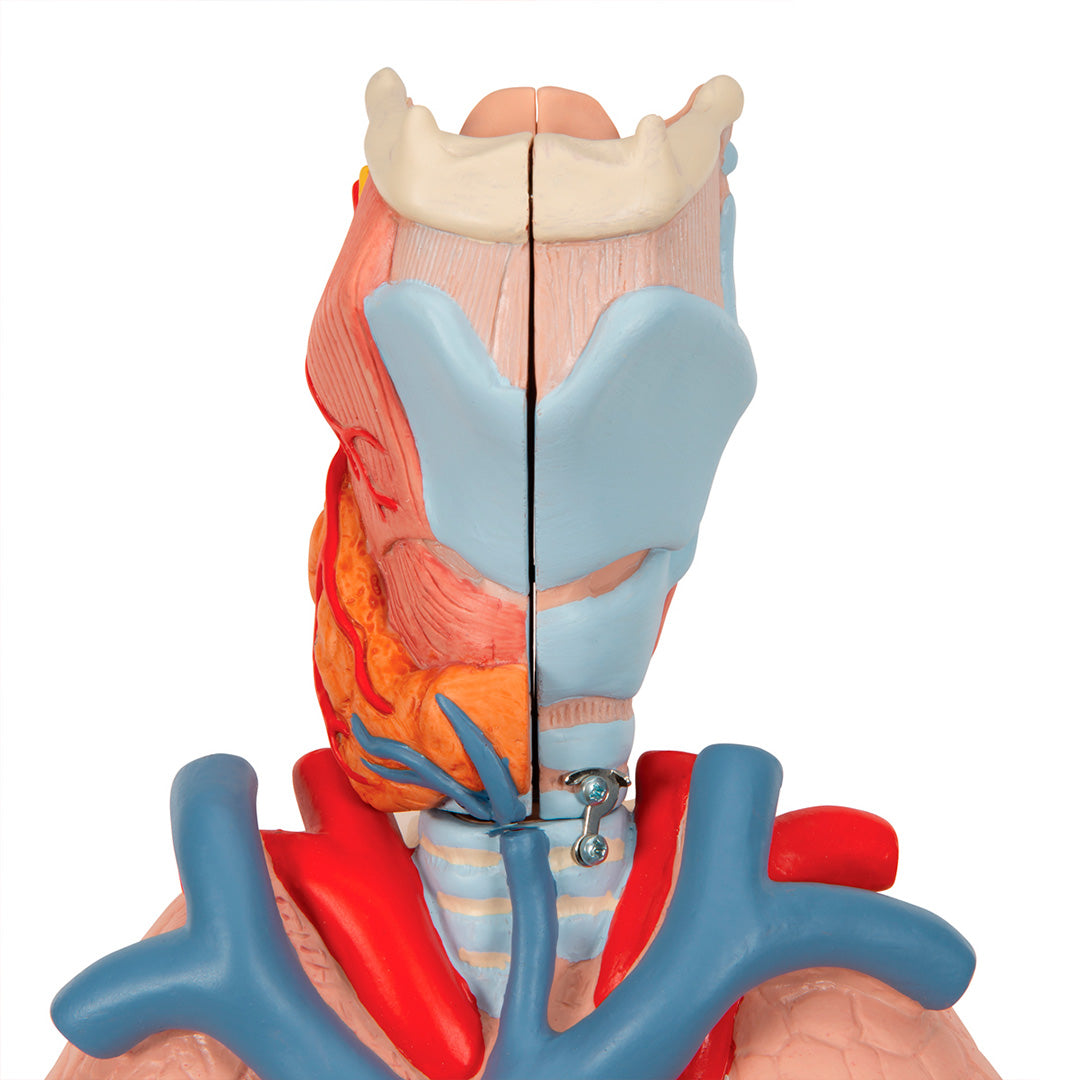

Modelo del pulmón, 7 piezas

Modelo del pulmón, 7 piezas

Descripción

Una sección aumentada y muy detallada a través de la mitad derecha del encéfalo, incluyendo una porción del cráneo.

Tiene dos lados y está coloreado delicadamente.